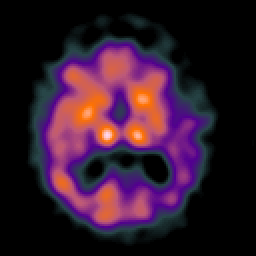

Alzheimer's disease: Perfusion SPECT -- Slice #25

[Home][Help][Clinical][Tour 1][Tour 2] Slice 25